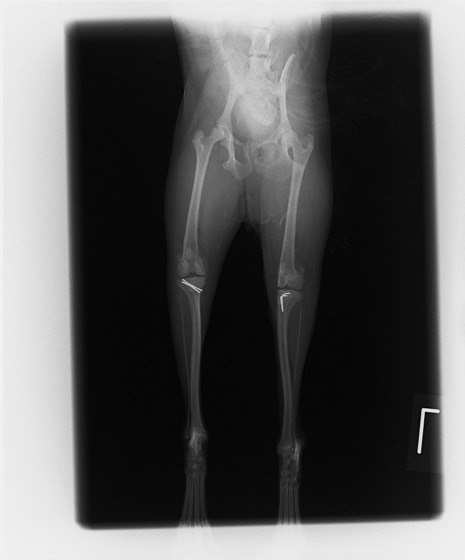

■ 症例20 ポメラニアン 8ヶ月 1.8kg

左右膝蓋骨脱臼 グレードⅢ

2ヶ月前から間欠的跛行が認められ、両膝の膝蓋骨脱臼整復術を行った。

手技は縫工筋及び内側広筋の解放、脛骨粗面の外側転位、滑車ブロック形造溝術、内外側関節包の縫縮を選択し実施した。

右側の膝蓋骨脱臼は上記手技で整復されたものの、左側はそれのみでは膝蓋骨が浮く様子が認められた。その為、PDS縫合糸にて膝蓋靱帯を1糸のみ縫合し、靱帯の縫縮を行った。

膝蓋骨脱臼は膝関節における膝蓋骨の内外側の脱臼と定義されるが、時として単純な内外の脱臼ではなく、膝蓋骨が大きく前方に浮き上がるように脱臼する場合がある。特にトイプードルやポメラニアンといった犬種に多く認められる。

内側脱臼に加えて前方への浮き上がりを矯正する為に、従来より脛骨粗面転移により膝蓋靭帯を外方と下方に引っ張り、固定する方法を選択する。膝蓋骨の前方への浮き上がりが軽度の場合は、従来法ではなく関節包の縫縮で対応していた。しかし、一部の症例で膝蓋骨の動きが悪くなり伸展機構が円滑に機能せずロボット様歩行になるケースがあった。

その為、膝蓋靭帯自体を縫縮する方法を採用した。この方法により、膝関節の伸展機構を妨げず膝蓋骨の軽度の浮きを矯正することが可能となった。

本症例の経過は良好である